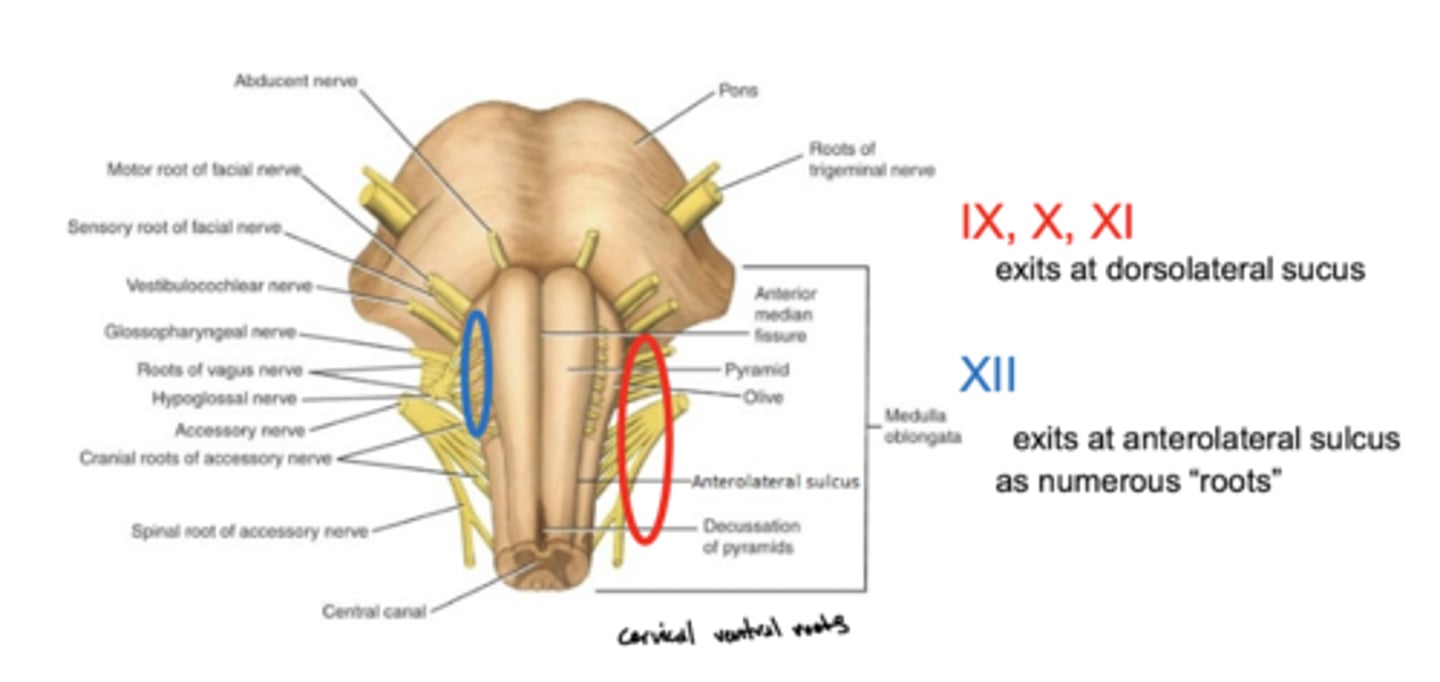

Where do CN IX, X, and XI exit the medulla oblongata?

exit the dorsolateral sulcus (

posterolateral sulcus)

3rd sulcus (counting medial to lateral) -- most lateral

Where does CN XII exit the medulla oblongata?

anterolateral sulcus -- as numerous roots

2nd sulcus (counting medial to lateral)